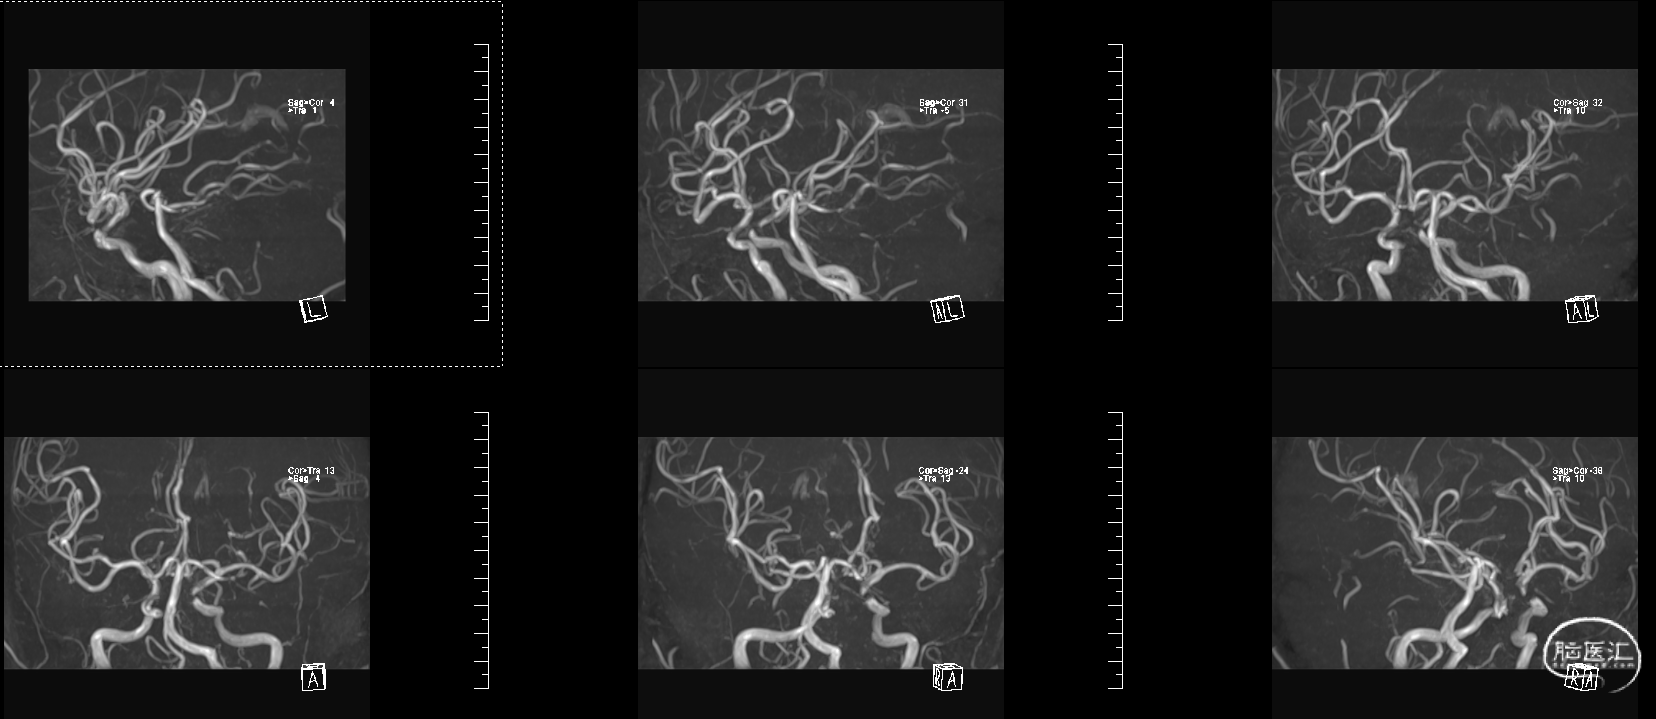

头颅MRI:左侧额顶叶急性脑梗塞;桥脑左份、双侧基底节、右侧脑室旁及双侧额叶多发腔隙性脑梗塞;双侧脑室旁及额顶叶轻度白质脱髓鞘;双侧上颌窦、筛窦、蝶窦炎;脑MRA示①右侧椎动脉纤细(变异)②左侧大脑后动脉P2段局部狭窄③左侧颈内动脉眼段局部严重狭窄④脑动脉轻度硬化改变,请结合临床及其他检查协诊。

溶栓同时急查头颅MRA

入院脑血管造影:

3、入院后查脑血管造影提示:左侧颈内动脉眼段重度狭窄。

左侧颈动脉眼段支架植入术:

1、先在左侧颈内动脉眼段小球囊预扩张,随后中间导管穿过狭窄处以便于支架通过,左侧颈内动脉眼段球扩支架成形术。